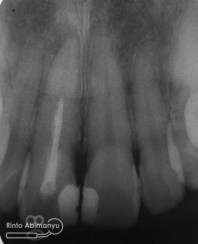

dan tidak lupa juga dibuat foto ronsen untuk melihat hasil perawatan ulang saluran akarnya…

Pengisian terlihat hermetis dan sepanjang kerja

Alhamdulillah semua rencana dari mulai perawatan ulang saluran akar sampai memperbaiki tambalan bisa selesai dalam 2 kunjungan dan hasil yang sesuai harapan… Pasien senang dan saya pun lebih senang 😀